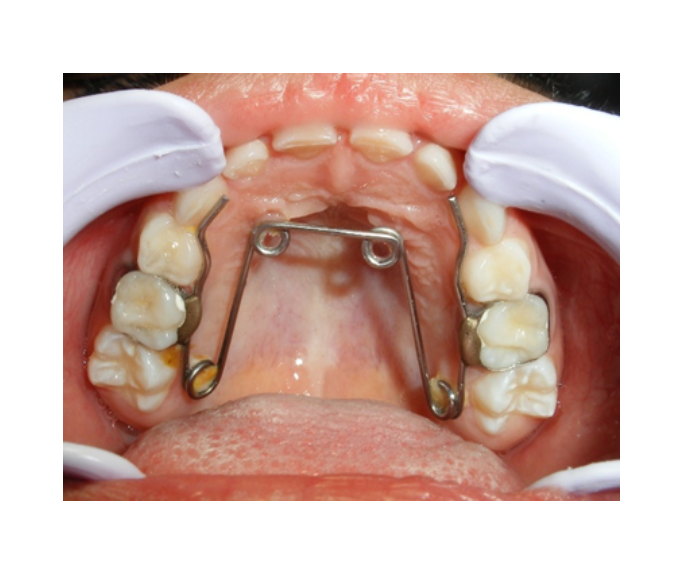

Mordida Cruzada posterior unilateral